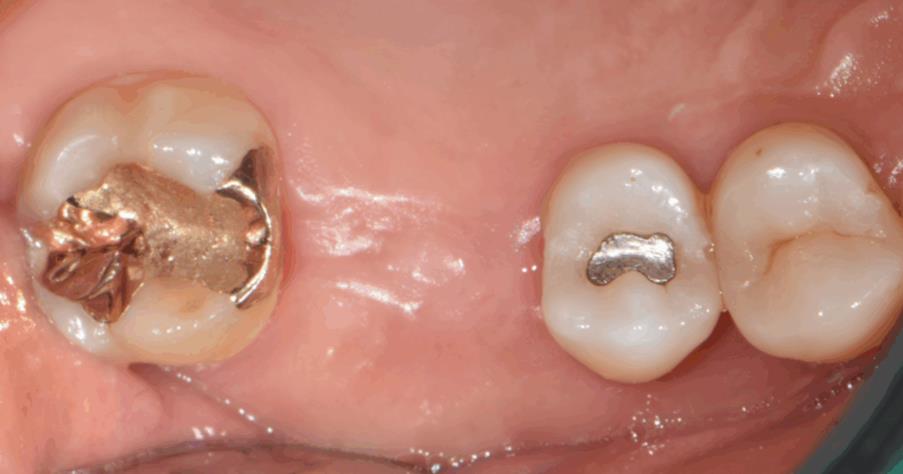

수술 직후 구내사진 – 절개 없이 깔끔하게 마무리된 수술 부위

마지막으로 보철물까지 안정적으로 장착해 환자분은 정상적인 저작 기능과 심미성을 회복하셨습니다.

보철물 장착 후 구내사진